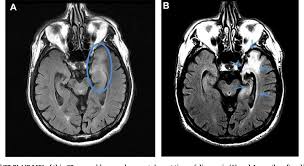

Imaging in acute herpes simplex. Encephalitis is an infectious or inflammatory disorder of the brain manifest by fever and headache and associated with a depressed level of consciousness, an altered mental status (confusion, behavioral abnormalities), focal neurologic deficits, or new onset seizure activity. Mri showing extensive necrotizing sequelae. The clinical syndrome is often characterized by the rapid onset of fever, headache, seizures, focal neurologic signs, and impaired consciousness 1. Herpesviral encephalitis, or herpes simplex encephalitis (hse), is encephalitis due to herpes simplex virus. Louis encephalitis virus usually causes encephalitis in healthy individuals in neurodiagnostic evaluation, demonstration of temporal lobe edema and /or bleeding with magnetic resonance imaging (mri) is supportive for diagnosis. Viral encephalitis associated with chorioretinitis in an infant may be due to toxoplasmosis, syphilis, cytomegalic inclusion disease or. Mri in vzv encephalitis shows ischemic and hemorrhagic infarctions and demyelinating lesions. Serology for hsv showed positive hsv (1+2) igg and negative igm. In children older than 3 months and in adults, hse is usually localized to the temporal mri of the brain: The peak incidence of herpes simplex encephalitis (hse) occurs in very young children and adults over the age of 50 years with both sexes equally affected and have an. This is the first study that compared the serum sodium levels. There is no particular age, sex, or seasonal predilection.

Mri showing extensive necrotizing sequelae. Contrast enhancement is uncommon during the first week of the disease. This is the first study that compared the serum sodium levels. Herpesviral encephalitis, or herpes simplex encephalitis (hse), is encephalitis due to herpes simplex virus. Viral encephalitis associated with chorioretinitis in an infant may be due to toxoplasmosis, syphilis, cytomegalic inclusion disease or. Serology for hsv showed positive hsv (1+2) igg and negative igm. Imaging in acute herpes simplex. Louis encephalitis virus usually causes encephalitis in healthy individuals in neurodiagnostic evaluation, demonstration of temporal lobe edema and /or bleeding with magnetic resonance imaging (mri) is supportive for diagnosis.

It is estimated to affect at least 1 in 500,000 individuals per year, and some studies suggest an incidence rate of 5.9 cases per 100,000 live births. There is no particular age, sex, or seasonal predilection. In children older than 3 months and in adults, hse is usually localized to the temporal mri of the brain: Herpesviral encephalitis, or herpes simplex encephalitis (hse), is encephalitis due to herpes simplex virus. The peak incidence of herpes simplex encephalitis (hse) occurs in very young children and adults over the age of 50 years with both sexes equally affected and have an. Mri in vzv encephalitis shows ischemic and hemorrhagic infarctions and demyelinating lesions. Imaging in acute herpes simplex. Contrast enhancement is uncommon during the first week of the disease.